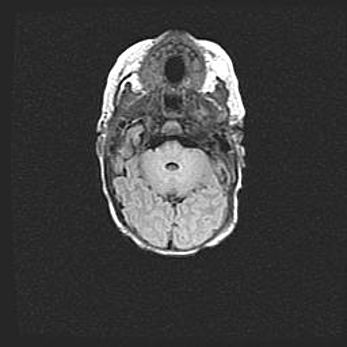

Церебральная ишемия II.

Возраст: 5 дней

Вес: 3400 г

Пол: женский

Окружность головы: 35 см

Срок гестации: 39 недель

Церебральная ишемия – это заболевание, характеризующееся недостаточностью (гипоксией) либо полным прекращением (аноксией) снабжения мозга кислородом по причине закупорки одного или нескольких сосудов. Это приводит к  что метаболическим расстройствам различной степени тяжести в тканях головного мозга, развитию коагуляционных некрозов и гибели нейронов.